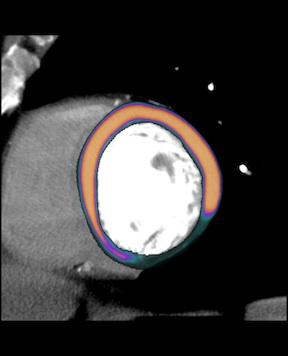

GE Healthcare image showing a myocardial perfusion overlay, based on contrast attenuation in the tissue, on its parent CT scan.

CT cardiac exams use iodine contrast injections to enhance the blood. All the vendors that developed CT perfusion analysis software measure the amount of contrast present in the myocardium at various stages of the cardiac cycle. Contrast attenuation maps are created, which can be plotted on a bulls-eye or overlaid on anatomical, multi-planar images of the left ventricle. These color maps show the amount of iodine (and thus the amount of blood) in the tissue. Areas of low contrast attenuation match areas of poor perfusion due to ischemia or infarct, similar to the radiotracer sugar uptake by heart cells during nuclear exams.

The resulting images with the color overlay look very similar to PET perfusion scans, but with much better image resolution and anatomical detail. If an ischemic area is detected, the CT dataset can be used to immediately find the culprit lesion.